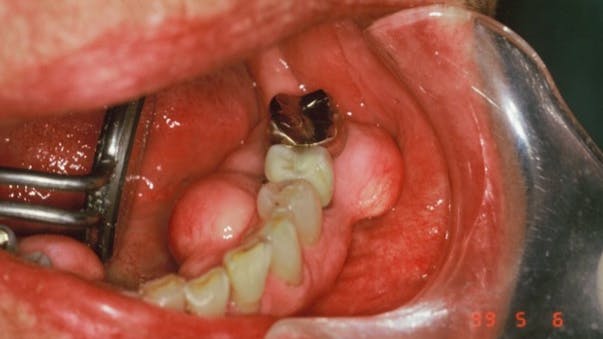

Another example is the formation of unique, highly polished, concavities at another focal point of high stress (figure 2). Kornfeld first observed this glassy sheen (1932) on both wedge-shaped NCLs and inverted cupolas.11 It is suggested that the glassy sheen is due to positive ions from the compression of apatite crystals, the piezoelectric effect.